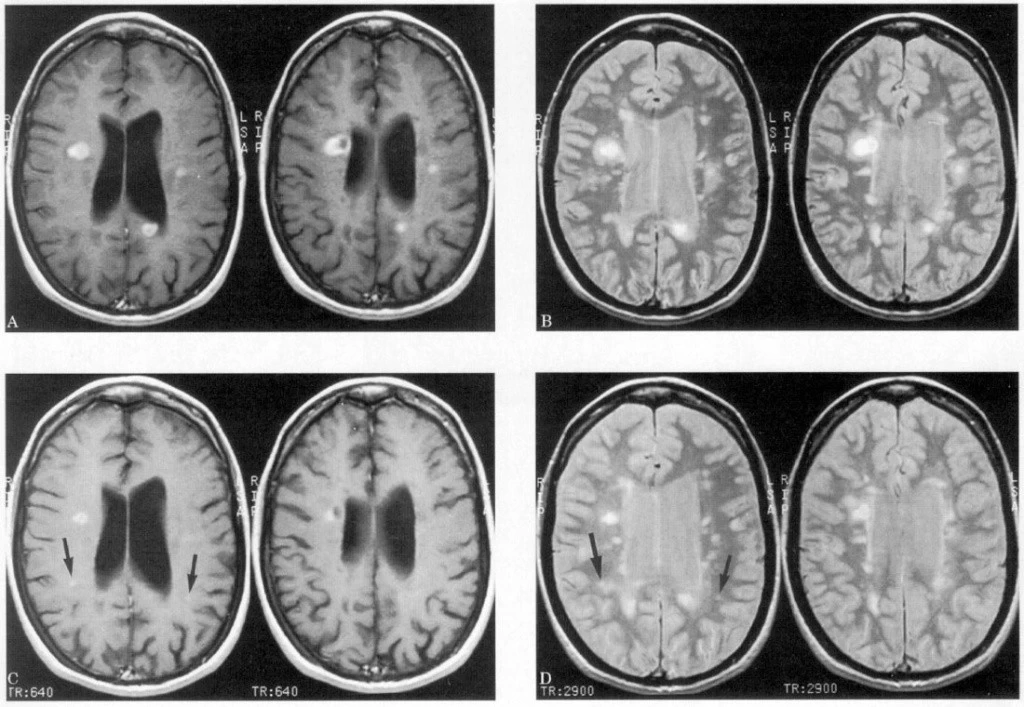

Магнитно-резонансная томография обнаружит истинно мозговые проблемы, возможно дополнение обследования контрастированием, модуляцией программ (сосудистая программа, послойные срезы, цветовые фильтры). КТ настроено на патологии костных структур, остеохондроз, объемную патологию, травмы; имеет лучевую нагрузку, в чем уступает МРТ-поиску.